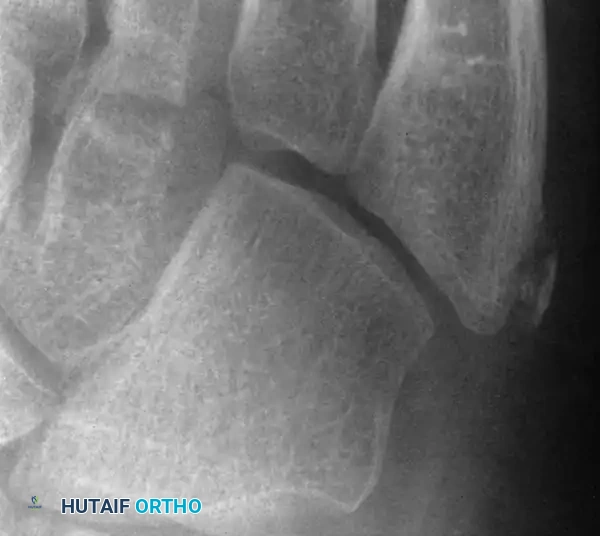

The secondary center of ossification is a small, shell-shaped fleck of bone oriented slightly obliquely with respect to the metatarsal shaft, located on the lateral plantar aspect of the tuberosity. Anatomical dissections confirm that this ossification center is embedded within the cartilaginous flare into which the peroneus brevis tendon inserts. Repetitive inversion stresses and the forceful pull of the peroneus brevis during athletic activities (running, jumping, cutting) lead to microavulsions and subsequent inflammation of the apophysis.

Ossification of the epiphysis on the fifth metatarsal shaft.

Standard anteroposterior and lateral radiographs often fail to visualize the lesion adequately; an oblique view is mandatory. Hoerr et al. demonstrated that this epiphysis is visible on 99% of oblique radiographs in this age group. Imaging typically reveals enlargement, widening of the cartilaginous-osseous junction, and occasionally fragmentation of the epiphysis.

Enlargement and fragmentation of the epiphysis characteristic of Iselin disease.